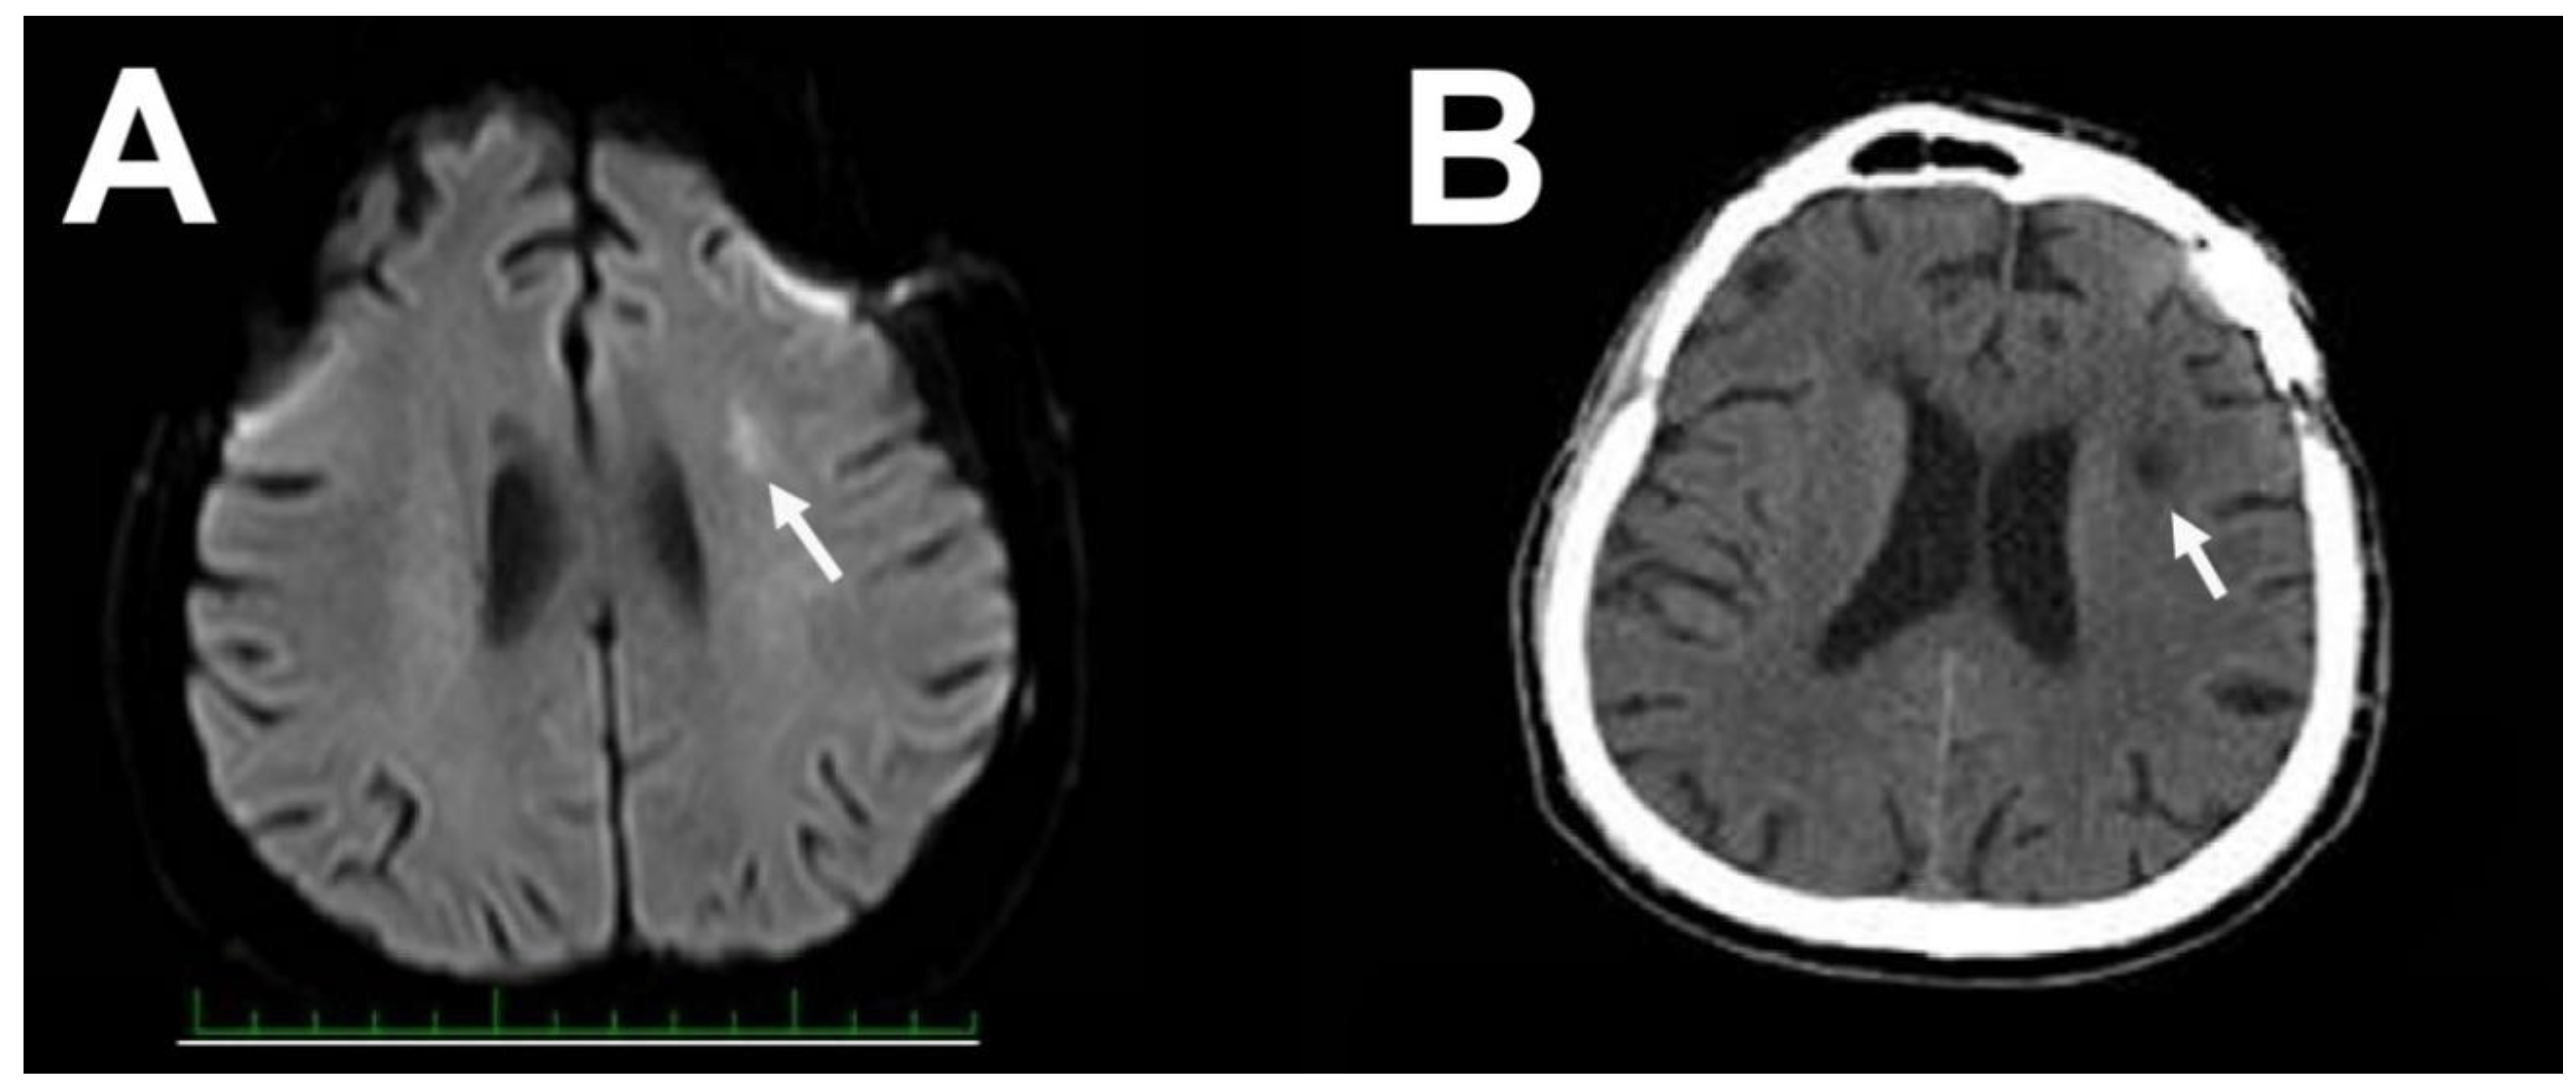

2. Case Report 1

3. Case Report 2